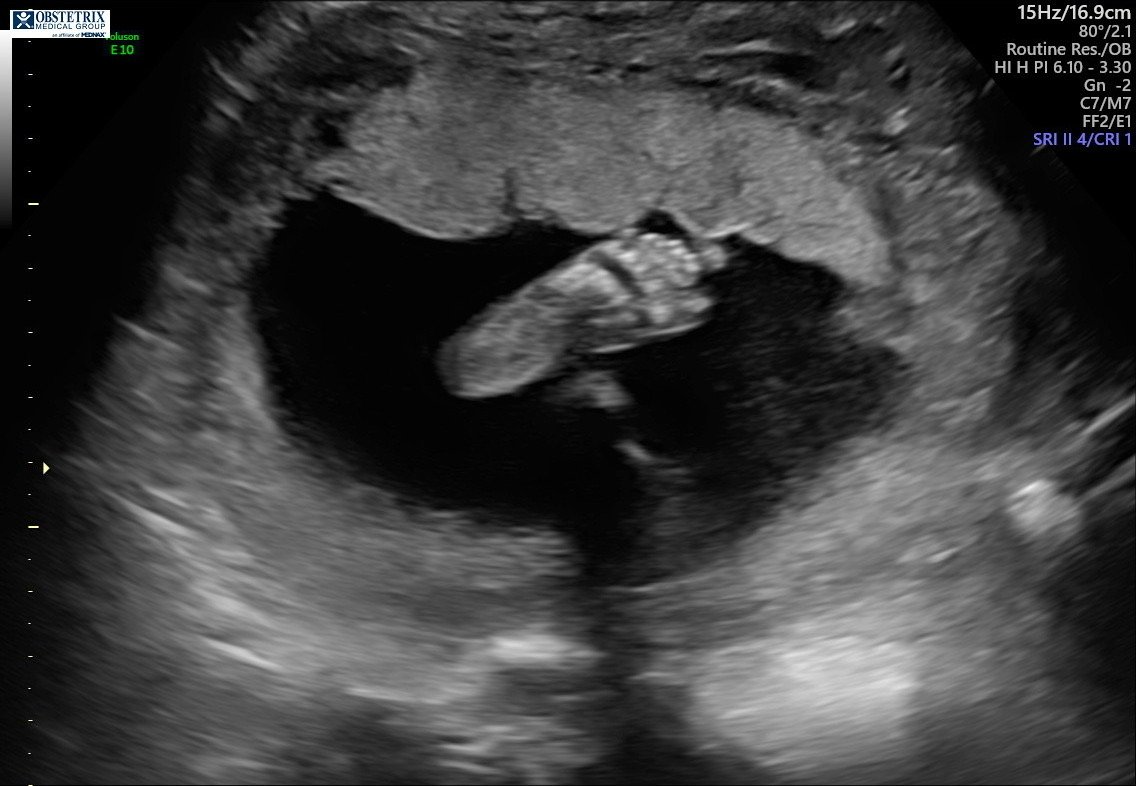

I’m measuring right on track at 23 weeks. Our baby weighs 1 lb 3 oz—WOW. I cannot believe our baby already weighs over a pound. And the best news of all? My cervix is holding like a rock. PRAISE BE!

We also got to see our little pumpkin in live 3D, which was such a special moment. Our baby is getting stronger and stronger every single day—and I know this because the kicks and punches are becoming more powerful by the day. It’s truly the best feeling in the world… until I’m laying down trying to go to sleep, LOL. Baby definitely likes to be active while mommy is resting.